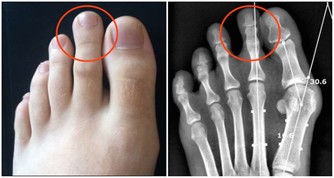

人老先老腿,腿上的筋結多了會引起很多的問題,我們在正常行走或在上下樓梯時,突然感覺膝關節吃不住勁,腿發軟,差點跪下,很多內科疾病也和腿上的筋結有關。

我們可以用手指在內外膝眼二個位置按揉,會發現手下有咕嚕咕嚕的感覺,膝關節過伸或勞累後疼痛,這就是膝蓋筋結。

把膝關節伸直看一看,如果膝眼是凹陷的,說明你的膝關節還可以,如果你的膝眼鼓起來了,摸到了硬硬的筋結,並且按著還有些疼,就說明膝關節退化的比較嚴重。